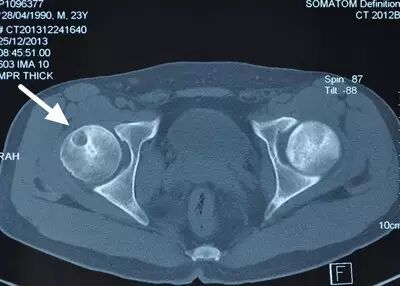

II期病人有髋部症状,磁共振出现异常,X线片显示股骨头出现透光和硬化改变

III期磁共振出现异常,X线片显示软骨下塌陷(新月征),股骨头内出现空洞,股骨头没有变扁

II期和III期的患者治疗方法相同,因为此时股骨头虽然还没有变形,暂时还不需要行人工关节置换术,但是股骨头已经出现空洞,随时股骨头就会塌陷变形,所以单纯的股骨头减压术是不能达到治疗效果的。这时就需要在股骨头减压的同时,植入一根支撑棒,顶住股骨头空洞区,防止股骨头在负重的情况下过早塌陷。其他治疗同之前相同,口服以上药物,定期复查,密切观察病情发展,尽量避免重体力劳动和爬山爬楼。

以上为股骨头坏死减压加支撑棒植入术示意图和术后X线片